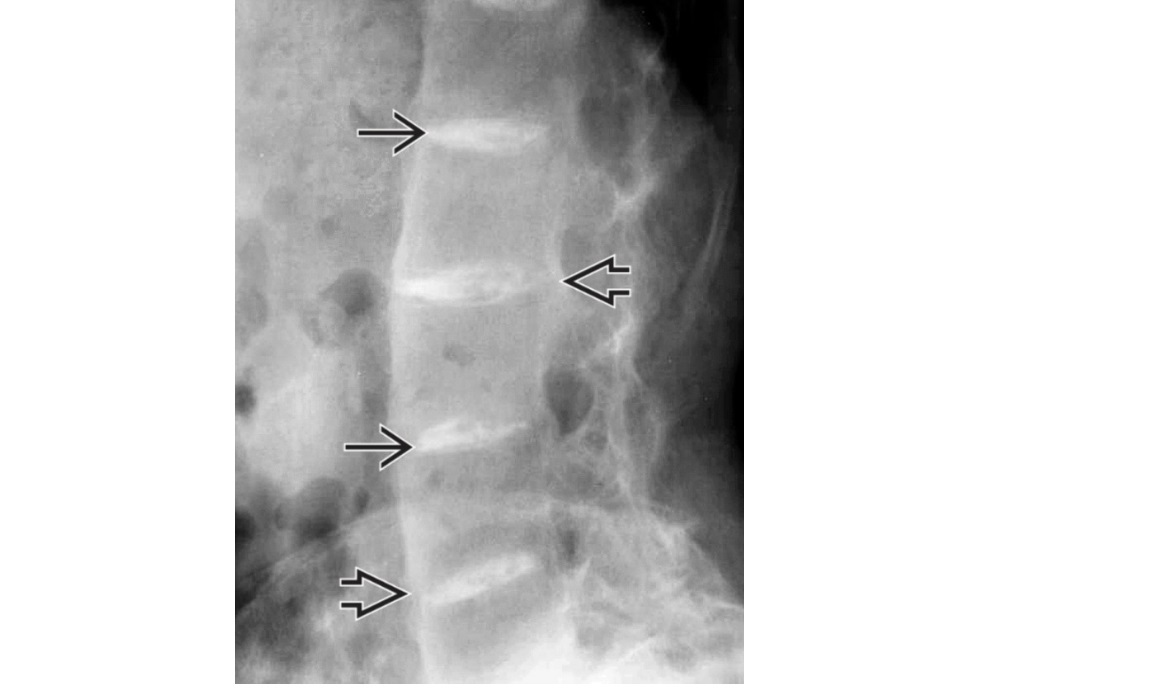

Chondrocalcinosis, premature OA changes and dark pigmentation in skin, particularly the ears?

A

Alkaptonuria / oschronosis

Nb Can be diagnosed in infancy - nappies stained black from urine.

AR condition. Excessive levels of homogentisic acid (HGA), affinity to accumulate in connective tissues.

Calcification and destruction intervertebral discs.